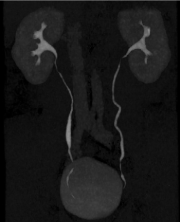

Qualitative evaluation: (Figures 5, 6)

Figure 5. Qualitative evaluation

Figure 5a. Excretory WV mode –sagittal view –result of the automatic stitching (a1). The junctions between volumes are recognized at certain levels (→ white arrow); after additional manual stitching (a2); the junctional zones have disappeared.

Figure 5b. Qualitative evaluation between helical acquisition unenhanced (b1) and excretory WV mode (b2). There is no visual difference for a clinical purpose between those two acquisition modes.

Figure 6. Clinical cases

Figure 6a. Normal patient (follow up after ablation of a bladder excretory tumour)-antero posterior MIP projection. The ureters are entirely evaluated without disruption.

Figure 6b. Duplicated excretory system with a urinary stone in the upper part of the lower excretory system. The ureter above the stone is collapsed due to the pathological process. Note that there is a discontinuity (↑ white arrow) of the lower pole of the kidneys, but it does not interfere for the right diagnosis.

Agreement between the two readers was excellent with a k correlation coefficient as high as 0.89. The intervention of the third reader was required in 2 cases. For image quality, our results according the subjective scale were as follows: score 1: poor (no case), score 2: fair (no case), score 3: good (14 cases) and score 4: excellent (31cases).

Concerning the quality of the stitching based on the continuity of the ureter, it was found discrepancies between the different volumes. We have found between the first and second volume at the upper level of the abdominopelvic region the following results: 82%,15% and 3% of cases for point 1, 2 and 3, respectively. For the three lower volumes, the final stitching was always excellent and rated 1 in 44 cases (except in one case with point 2).) No cases were uninterpretable. The diagnosis was performed without any ambiguity.